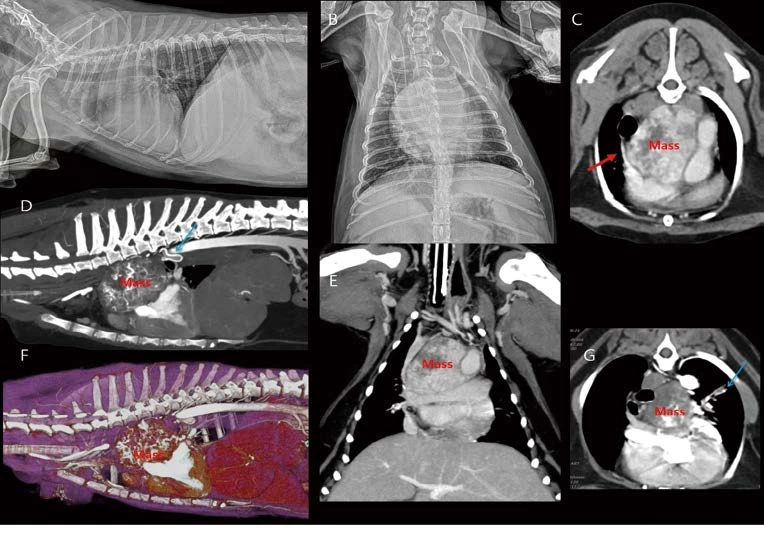

%EB%8C%80%ED%95%9C%EC%88%98%EC%9D%98%EC%82%AC%ED%9A%8C%EC%A7%80_24.png?type=w1

16살 중성화 암컷 10.5kg Beagle의 건강검진에서 심장 종양이 관찰되어 의뢰되었습니다. 흉부방사선 검사에서 right side cardiomegaly 및 heartbase 또는 aortic body 위치에서 둥근 밀도 증가 영역이 관찰됩니다(A, B). 심초음파에서 소량의 심낭수 및 heartbase 위치의 커다란 종괴가 관찰됩니다. CT 검사에서 우심방과 전대정맥을 압박하는 커다란 이질적 heartbase tumor가 관찰됩니다(C, D E, F, G). 또한 , heartbase tumor와 관련하여 폐혈관 내 혈전(G), left bronchoesophageal arterial hypertrophy 소견(D)도 추가로 관찰됩니다. Heartbase tumor에는 chemodectoma가 주로 보고되어 있습니다. Brachycephalic dogs에서 incidental findings으로 관찰되는 경우가 많으며, Non brachycephalic dogs에서도 은근히 관찰됩니다. 종괴의 정확한 진단을 위해서는 조직 검사가 필요하나, 현실적으로 조직 검사가 어려운 경우가 많기 때문에 모니터링을 통해 가진단을 내리게 됩니다. Chemodectoma는 일반적으로 benign하나, RA, CrVC 등 주변 구조물을 심하게 압박하는 경우(C)에 cranial vena cava syndrome의 증상을 보일 수 있습니다. 또한 left bronchoesophageal arterial hypertrophy(D), esophageal varices, 혈전(G) 등의 complications이 발생할 수 있습니다. 환자 경과에 대한 면밀한 모니터링이 필요합니다. CT에서 Incidental finding으로 heartbase tumor가 관찰되었던 환자들의 흉부방사선 검사를 다시 평가하면, 안 보이던 종괴 음영이 잘 보이게 되는 ‘아차!’ 경험을 하게 됩니다. 다양한 이로 CT 촬영을 하는 환자들을 기존 방사선 검사 또는 초음파 검사와 비교하다 보면 많이 배우게 되는 것 같습니다.